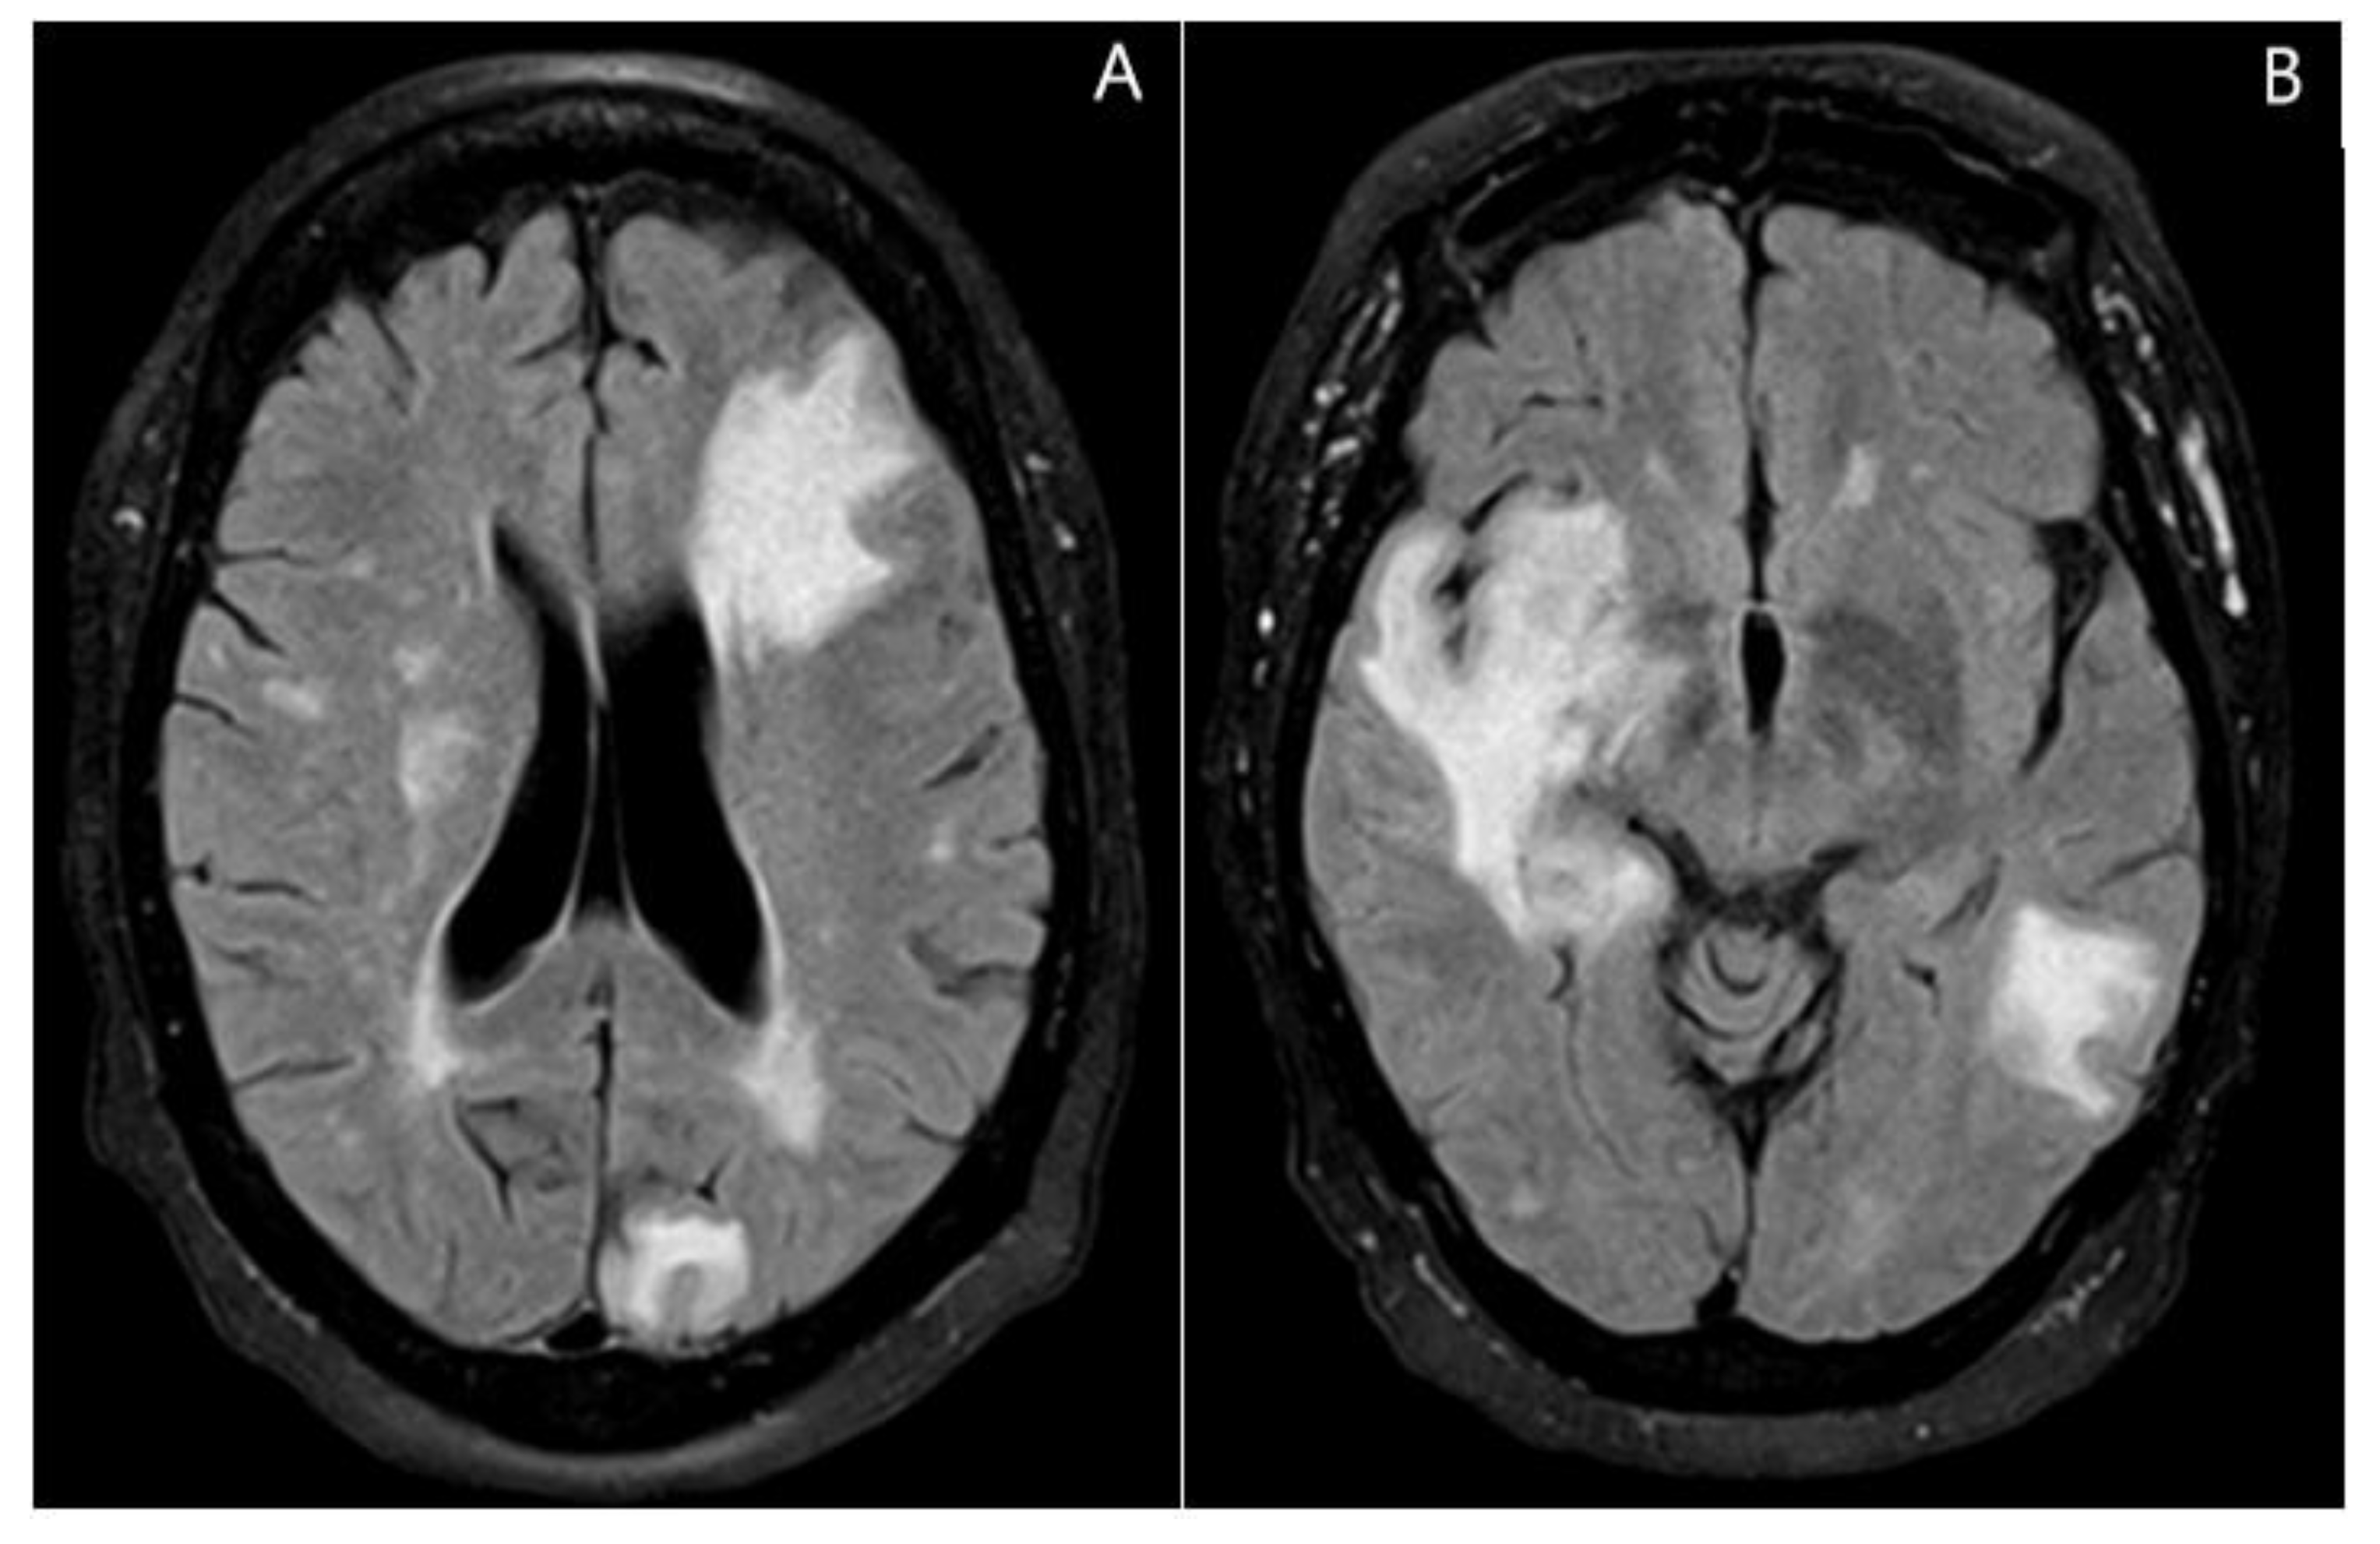

2. Case Presentation